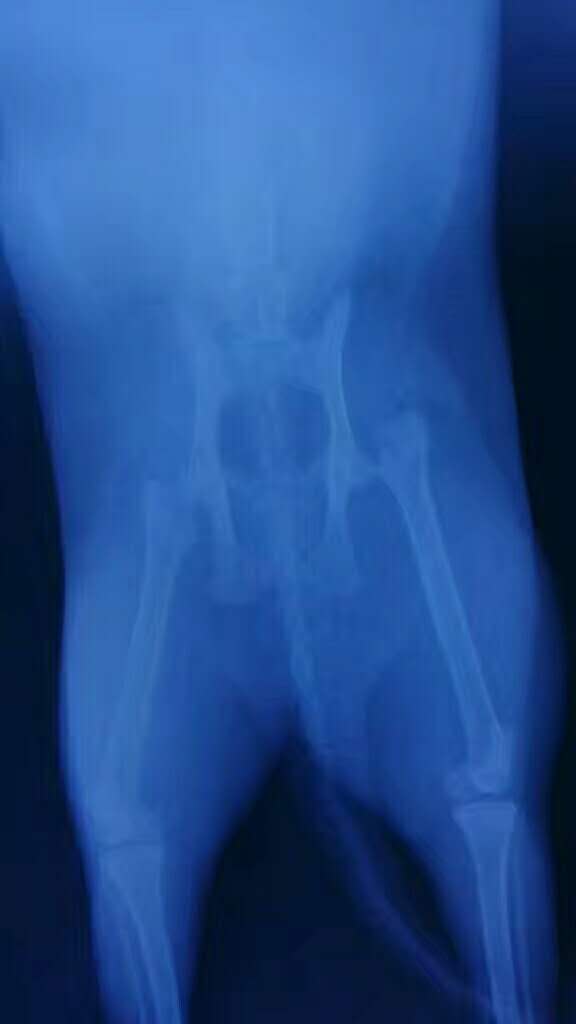

股骨頭斷裂矯正

小白,田園貓,因外傷導(dǎo)致骨股頭斷裂,實施手術(shù)矯正。